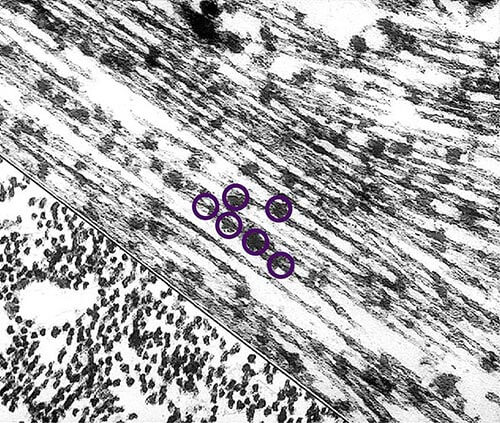

More About Tangles

Tangles destroy a vital cell transport system made of proteins. This electron microscope picture shows a cell with some healthy areas and other areas where tangles are forming.

In healthy areas:

In areas where tangles are forming:

Nutrients and other essential supplies can no longer move through the cells, which eventually die.